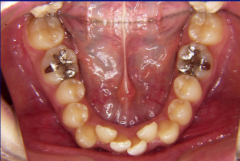

装置装着前

装置装着後